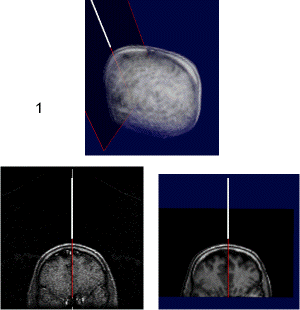

Figure 1:

MR data set with a light guide positioned within a tumor selected for laser irradiation

Figure 5:

upper: overview of scull with interventional device and associated scan plane;

left: plane from interventional MRI scan (low quality);

right: plane from preoperative MRI scan (high quality).

Quicktime movie (180 KB) showing positioning of device.